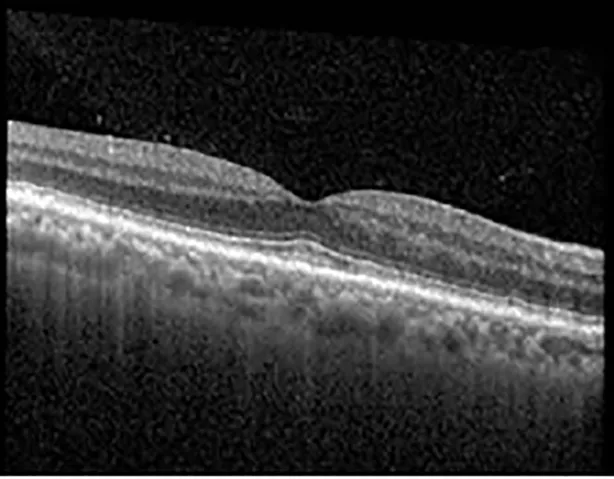

The patient began treatment with oral pemigatinib daily and was followed up for an ophthalmic examination during the second treatment cycle approximately 5 weeks into the treatment process. The patient had at this stage received 28 doses of 13.5 mg per day, which was administered in cycles of 14 on-days and 7 off-days, and had no visual or ophthalmic complaints. The non-corrected VA was OD 20/30 + 1 and OS 20/20. The OCT examinations revealed subfoveal SRF bilaterally. The fundus examination was otherwise unremarkable outside the patient’s prior documented peripheral drusen. Repeat autofluorescence was overall unchanged, though a slight hypofluorescent ring may be visualized in Figure 2. The current pemigatinib protocol recommendation for asymptomatic patients suggests no dose modification; however, with worsening presentation or positive symptoms, it is recommended to withhold pemigatinib. After discussion with the patient’s oncologist, it was decided to continue the medication at this time. Serial monitoring of the patient’s symptoms, vision, and SRF were conducted on specific days during active treatment cycles and days off-cycle to monitor the SRF. Subsequent evaluations demonstrated complete resolution of SRF while off-cycle, and asymptomatic re-accumulation of fluid while on-cycle with varying levels of VA. (Table 1) As we see demonstrated in the table below, in the later stages of the active cycles, such as day 13 of 14 of cycle 2, day 13 of 14 of cycle 3, day 13 of 14 of cycle 4, and day 14 of 14 on cycle 5, the patient’s VA showed no correlative changes based on the presence of SRF. The fluctuations in the patient’s VA certainly occurred, but were likely to be secondary to surface changes, as certain off-cycle days actually presented with lower acuities than days when the SRF was present on OCT examination.

| Cycle, day, on/off | VA OD; OS | CMT OD; OS | OCT OD | OCT OS |

| Cycle 3, day 6/14, on | 20/40−1; 20/30−1 | 306; 301 | ![]() | ![]() |

| Cycle 3 day 13/14, Oon | 20/50+1; 20/30−2 | Poor tracing; 376 | ![]() | ![]() |

Highlights the visual acuity, central macular thickness, and the physical OCT of the macula for this patient in both the right and left eyes during various stages of the patient's chemotherapy treatment cycle.